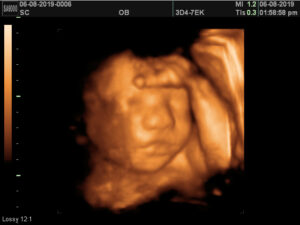

Our 4d Baby and 3D ultrasound and sonogram sessions allow you to see your baby in 2d, 3d, and 4d live motion with a 3D/4D/HD ultrasound at one of our Texas locations. 4 Baby serves Dallas, Fort Worth, Waxahachie, Ennis, Grapevine, Frisco, Flower Mound and Tyler Texas as well. We use ultrasound technology to bring your baby images to life. We provide large screens for you and your family to actually see what your baby is going to look like before they are born! Our amazing images make for a special experience. Bring your family to enjoy your 3d and gender ultrasound scan with you.

Our 3D, 4D and HD ultrasound packages provide a special experience for mother, parents and family to see your precious baby. We offer 3d sonograms and ultrasounds for twins. You will love the experience to view and share your 3D/HD ultrasound photos.Our machines are the best 2D, 3D, 4D and HD ultrasound machine available. The technology will give you unparalleled quality images of your baby.Combine your 4 Baby 3D Ultrasound, 4D Ultrasound & HD Ultrasound Imaging experience with our many other services. You may create a custom sonogram bundle with Maternity and Newborn photography and 7 week DNA gender blood testing. Take your 3d ultrasound experience to a whole new level today.

- Modern technology has allowed us to see your baby yawn or suck his thumb while still in the womb. Some baby’s will even open and close their eyes. With 3D ultrasounds and 4D sonograms, you can determine if your baby has Mom’s lips and Dad’s nose! Are you curious if your baby is a boy or girl? We can enlighten you with our ultrasound so that you can share this surprise announcement at your own gender party!